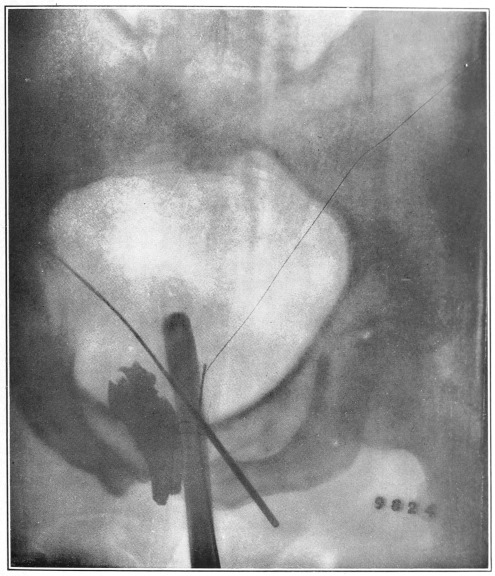

Nine Radiograph Illustrations Showing Mucus Channels and Cavities200

When disease exists we simply desire to open the contracted or obstructed canal. What can be better, in a therapeutic line, than the kindly distending influence of warm water to overcome the spasmodic closure of the diseased tube? In addition to the gentle dilatation the injected water occasions, the water creates or calls into activity the lost nervous impulse to evacuate, which impulse is a step toward the restoration of the lost normality.